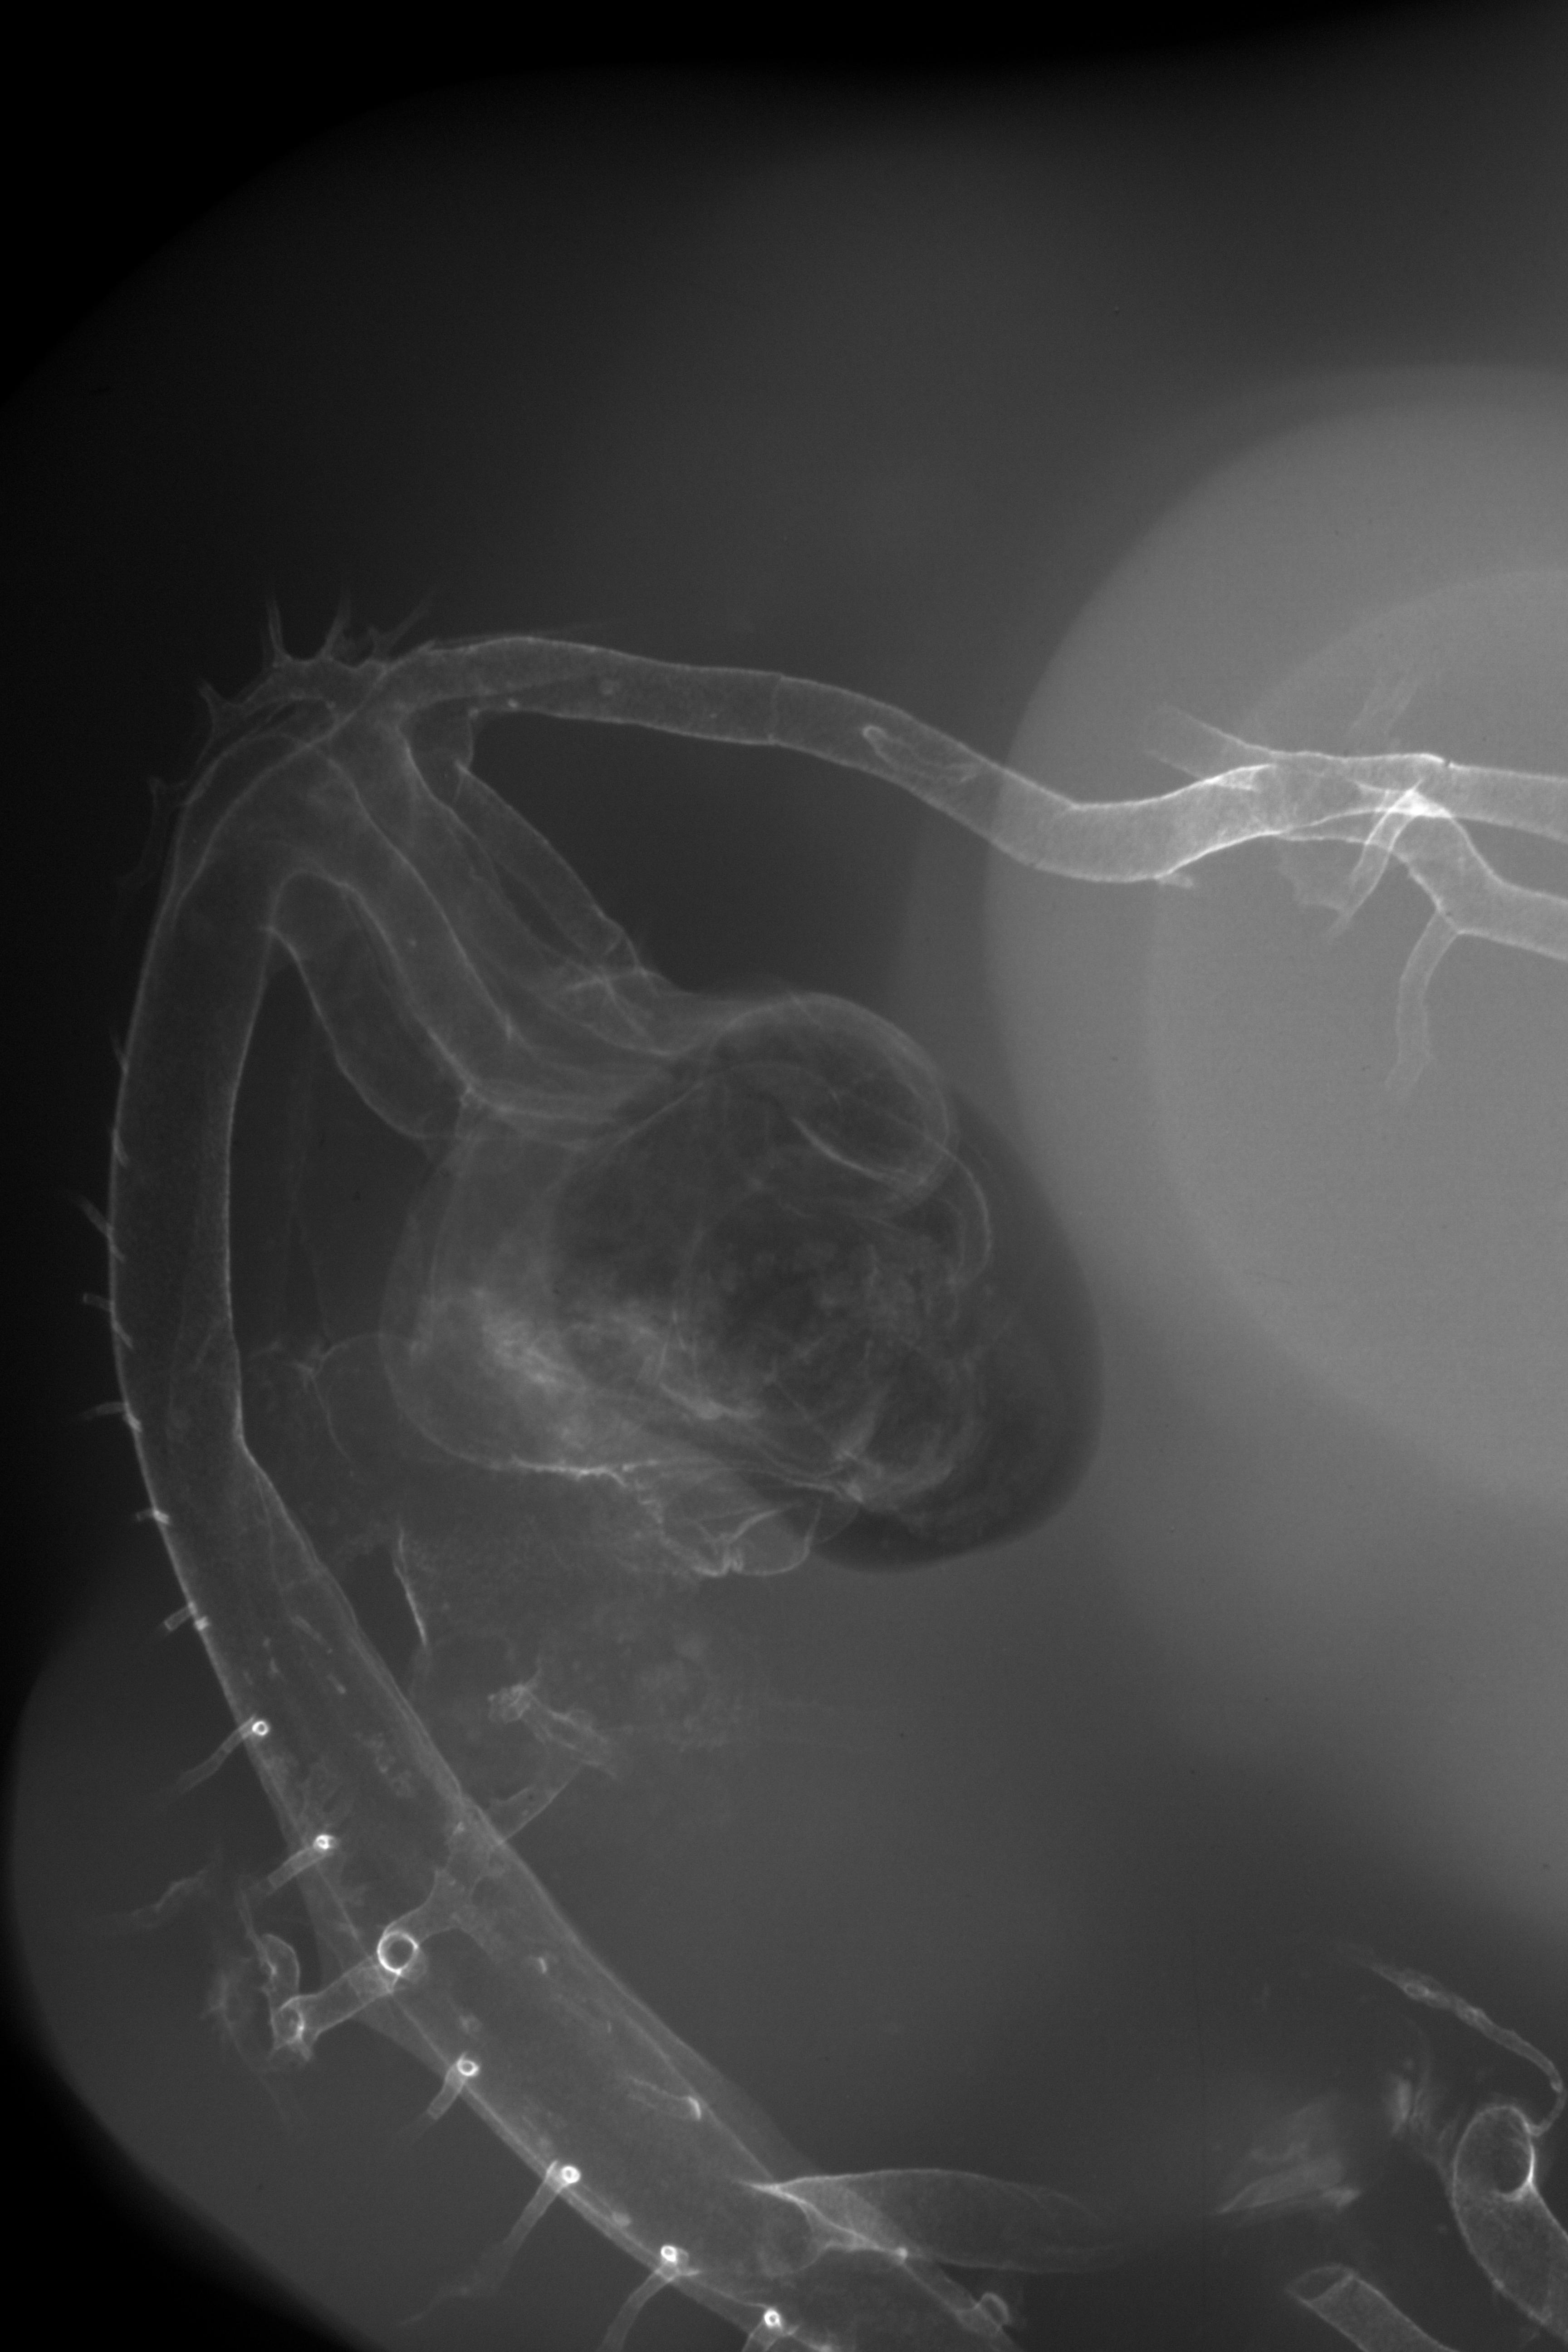

Chick Embryo Microangiography

Hamburger-Hamilton (HH) Stage 27 (approx. 5 - 5.5 days)

X-Ray Micrographs